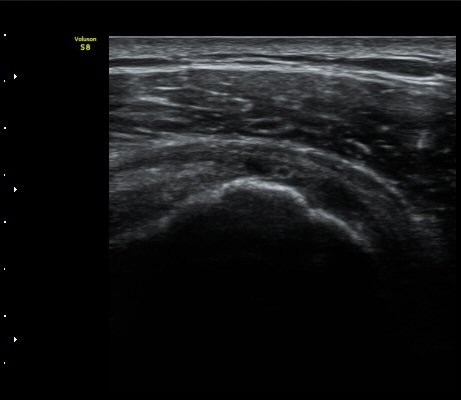

±Ø»ó°Ç³»Ãø Á¾´Ü¸é°Ë»ç¿¡¼­ ±Ø»ê°Ç ºÎÂøºÎÀÇ  ÀÛÀº ÆÄ¿­°ú Á¡¾×³¶ ºÎÁ¾ÀÌ °üÂûµÊ(±×¸² 2, 3).

±Ø»ó°Ç ¿ÜÃø Á¾´Ü¸é°Ë»ç ½Ã Á¡¾×³¶ ºÎÁ¾ÀÌ °üÂûµÊ(±×¸² 4).

±Ø»ó°Ç ±ÙÀ§ºÎ ±Ø»ó°Ç ³»ÃøÀÇ Àú¿¡ÄÚ ºÎÁ¾°ú Á¡¾×³¶ ºÎÁ¾ÀÌ °üÂûµÊ(±×¸² 5).

±Ø»ó°Ç ¿øÀ§ºÎ ±Ø»ó°Ç ºÎÂøºÎ ÀÛÀº ÆÄ¿­ÀÌ °üÂûµÊ(±×¸² 6).